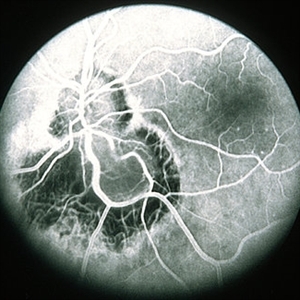

ToxocaraGgranuloma

Jun 30 2014 by Henry J. Kaplan, MD

Arterial phase fluorescein angiography of the patient with toxocara granuloma shows hypofluorescence in most part of the lesion and arterial supply to the lesion #2.

Condition/keywords: toxocara granuloma